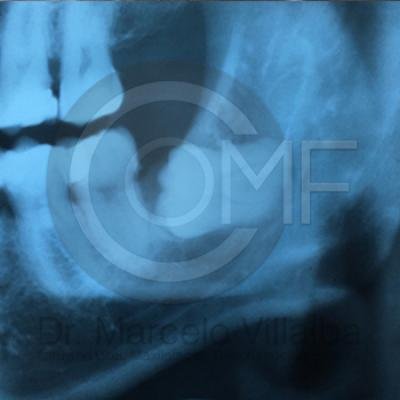

Generalmente en el momento de su erupción presentan procesos inflamatorios en la zona posterior de la cavidad oral, infección, dolor, movilidad de órganos dentarios, mal sabor en boca, mal olor en boca (halitosis), infección, incluso edema (aumento de volumen en tejido blando de la cara y/o boca) y complicaciones si no son atendidos. En el apoyo de diagnóstico se pueden requerir radiografías panorámicas y hasta tomografía en caso de ser necesarios.

Para el tratamiento de estas patologías se necesita en forma inicial estudios de laboratorio, radiografías o tomografías, estos estudios serán solicitados por el especialista a cada caso en particular, siendo su tratamiento quirúrgico bajo la modalidad de anestesia local o anestesia local más sedación consciente se puede realizar el procedimiento en corto tiempo y buen pronóstico.